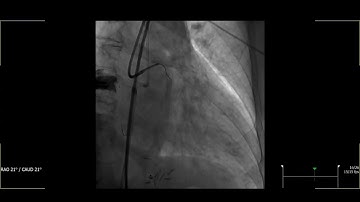

Circumflex CTO-PCI @ TCT 2022